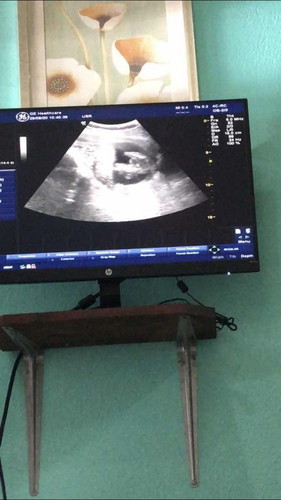

16 weeks 2 วัน หมอบอก 80% ผู้หญิงคะ

น้ำหนัก 158 กรัมแล้ว 😍